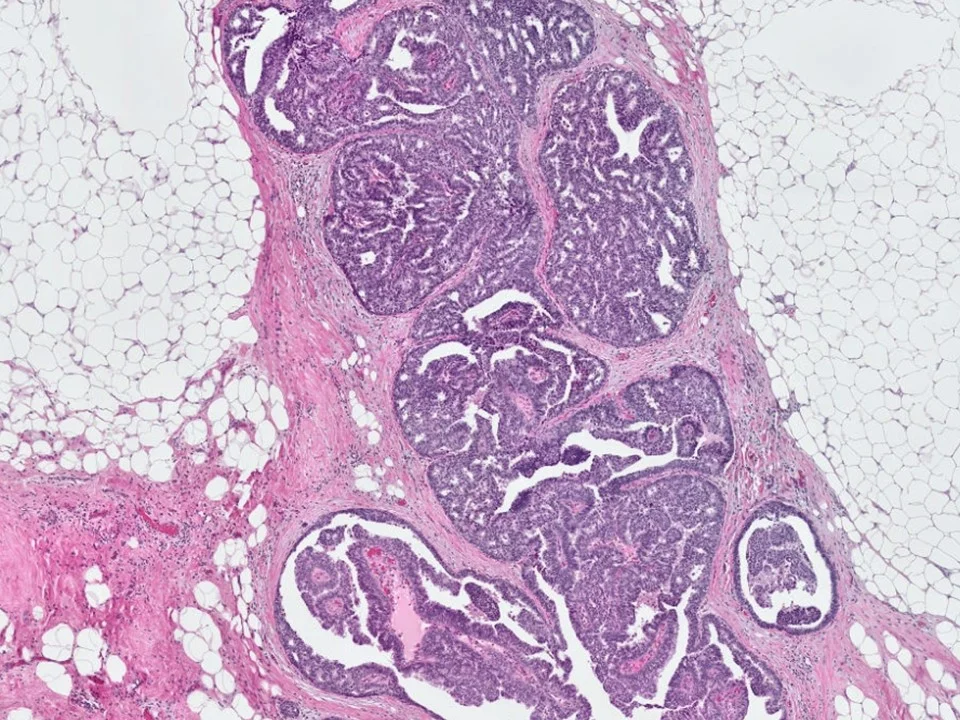

Malignant Phyllodes Tumor

Frond-like projections of cellular stroma covered by epithelium and myopeithelium protruding into epithelial-lined cystic spaces create a leaf-like appearance.

Malignant phyllodes have an infiltrative border (as pictured here), highly cellular stroma, stromal cells with moderate to marked nuclear pleomorphism, and prominent mitotic activity (>/= 10 mits per 10 HPF)